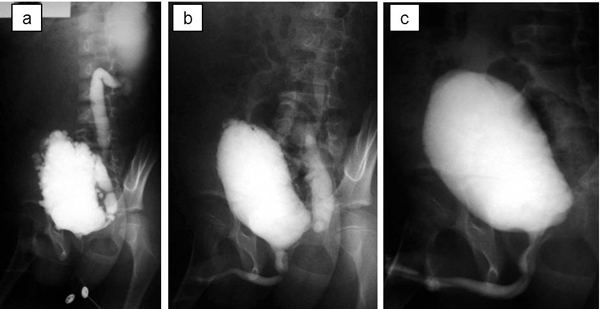

A 7-year-old boy was referred with persistent day-time incontinence and nocturnal enuresis in addition to severe bilateral hydroureteronephrosis on ultrasonography. He had a history of sepsis at two weeks of age although the details were unknown. Prenatal ultrasonographic findings were also unknown. He required clean intermittent catheterization because of voiding difficulty and significant postvoid residual urine. Voiding cystourethrography and diuretic renography revealed that he had VURD syndrome (Fig. 1a). Subsequently, he underwent transurethral incision of the valves. On postoperative voiding cystourethrography, the unilateral reflux remained unchanged although the bladder outlet obstruction was relieved (Fig. 1b). At 9 year of age, he underwent left nephroureterectomy. After one year, clean intermittent catheterization and anticholinergic drugs were discontinued because he had neither voiding nor storing problems on video urodynamic study (Fig. 1c). The estimated glomerular filtration rate was 123 ml/m/1.73 m2 at 15 year of age. Ultrasonography revealed right hydronephrosis that was grade 2 according to the Society for Fetal Urology (SFU) classification at 17 year of age.

Figure 1: Voiding cystourethrography; (a) before transurethral incision of the valves, (b) before left nephroureterectomy, (c) 7 months after nephroureterectomy |